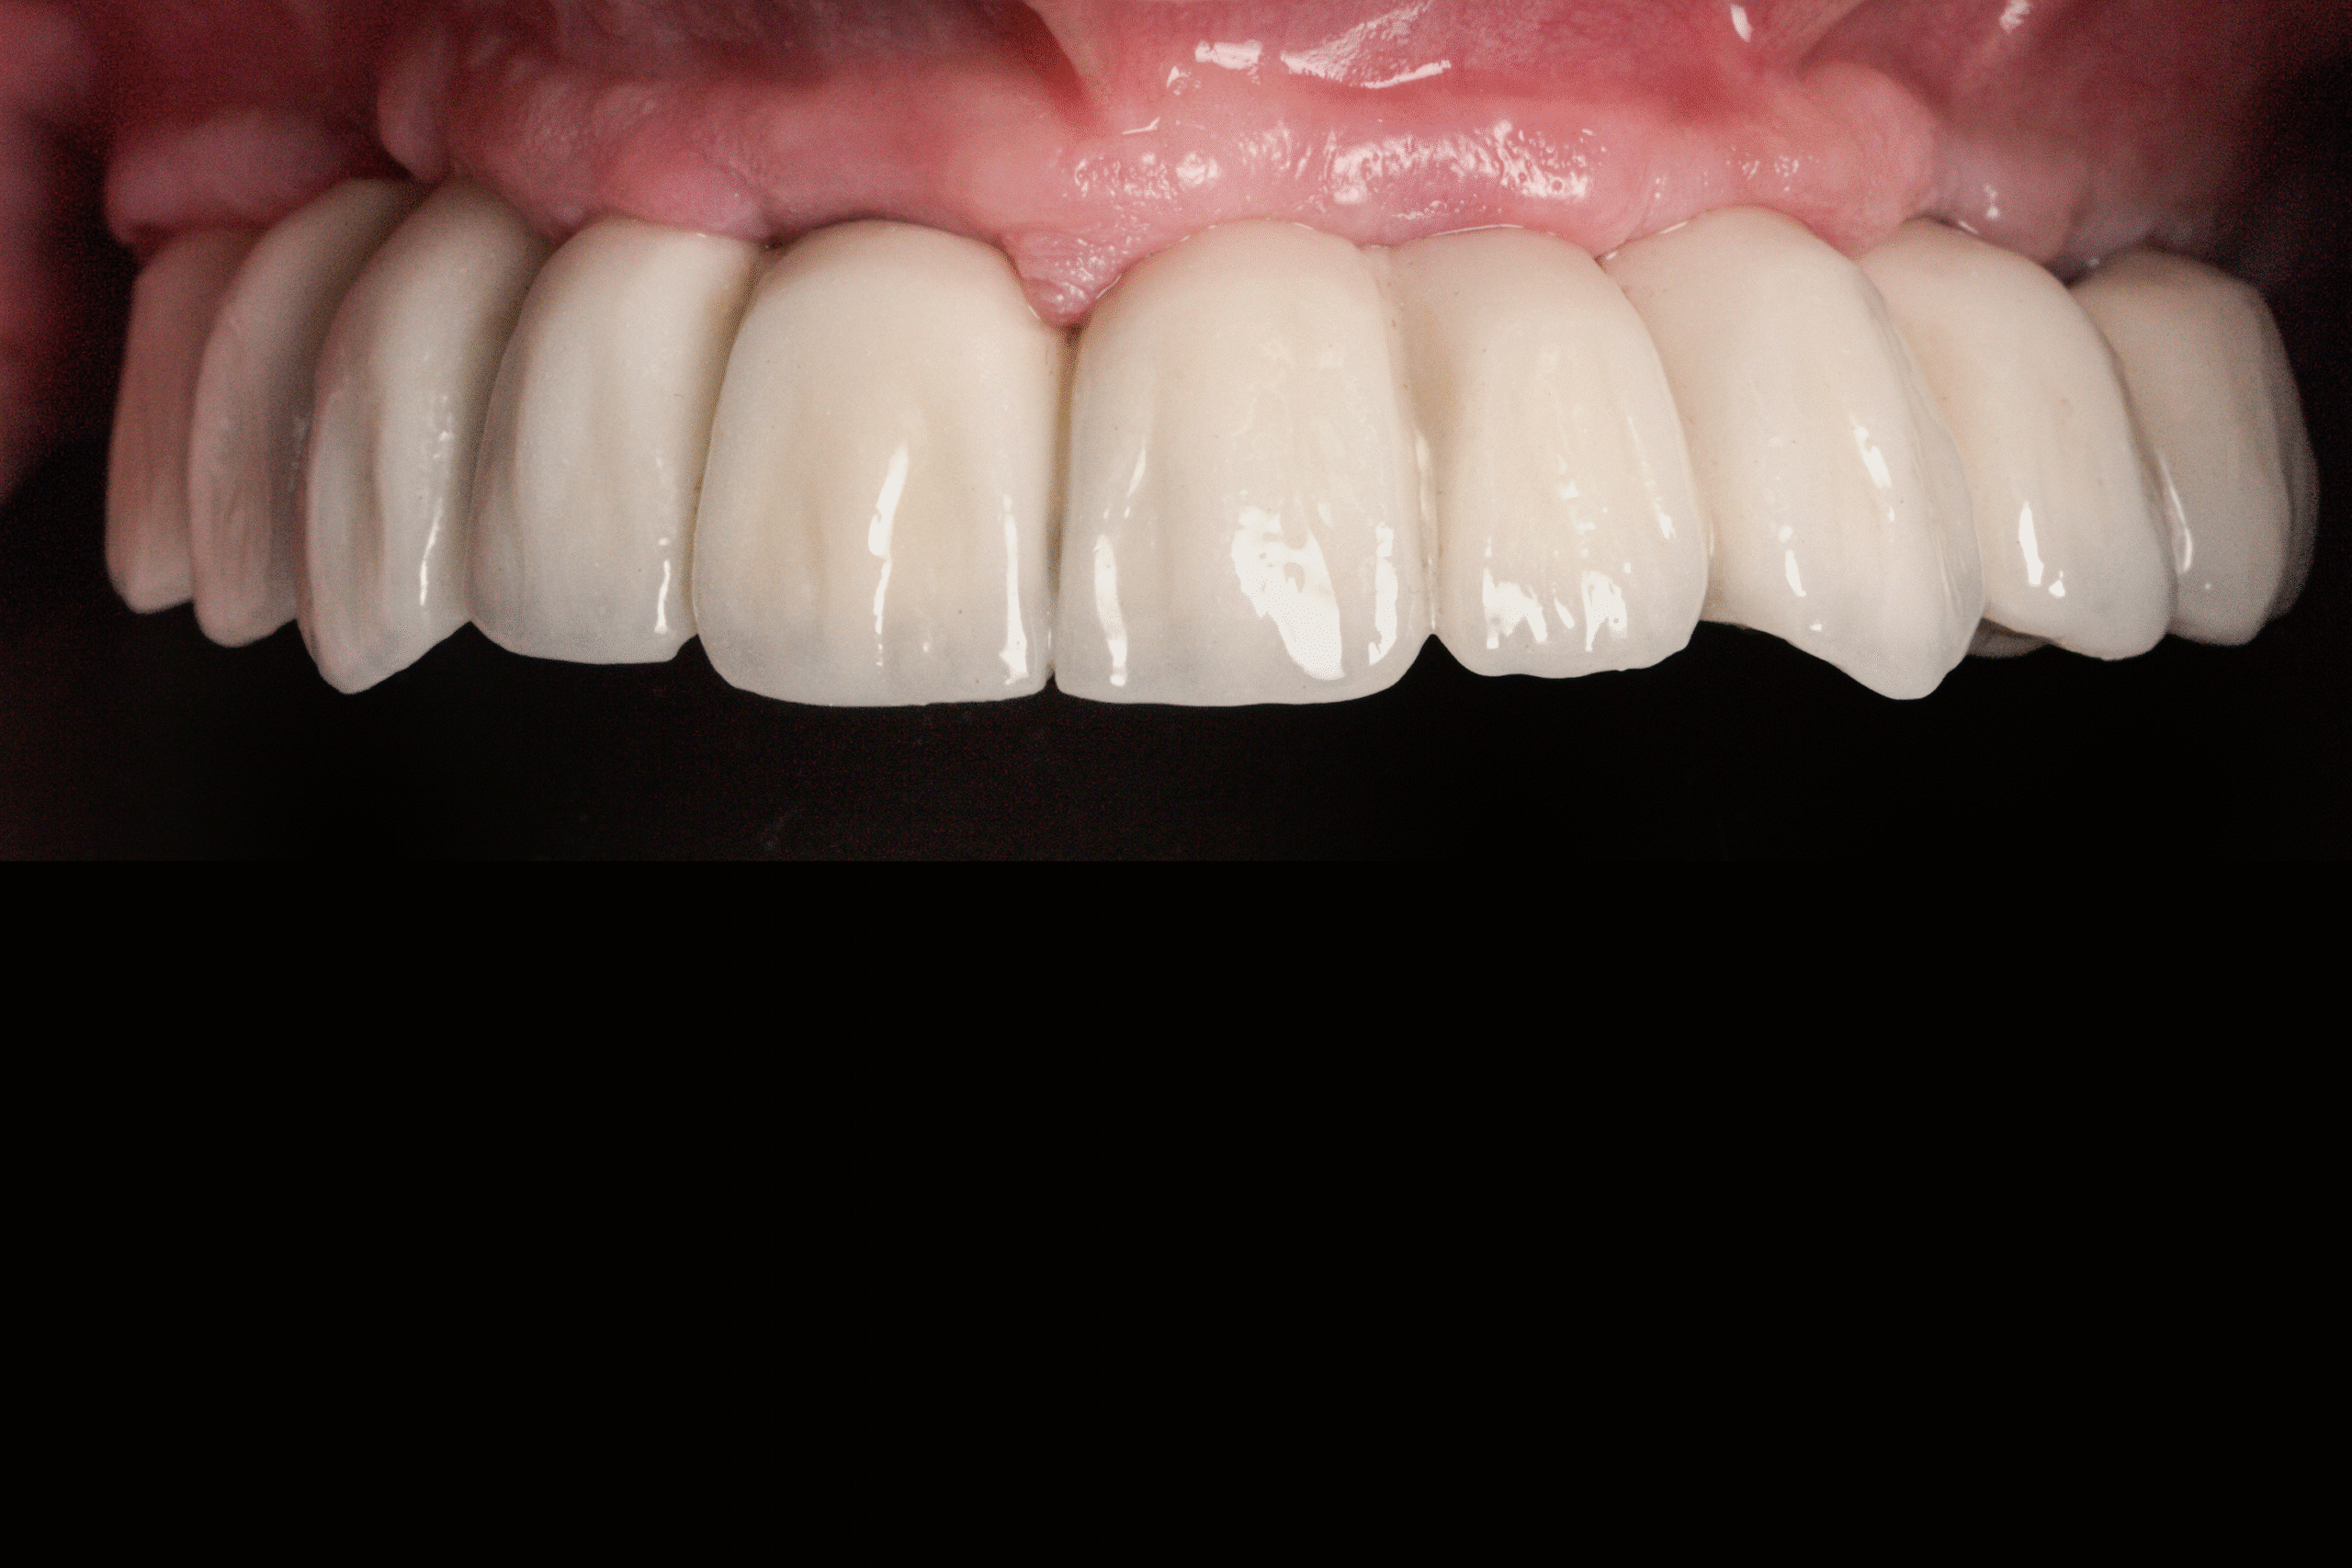

After

- Temporary fixed teeth fabricated to restore function and appearance

In only 3 hours, James received a complete upper-jaw reconstruction and a corrected lower-arch restoration using a fully flapless implant technique.

He left the clinic the same day with:

- A functional temporary smile

- A dramatically improved ability to speak and chew

This case illustrates how advanced digital planning and minimally invasive implant techniques allow us to deliver efficient, predictable, and life-changing results — even for patients with complete upper-tooth loss and failed previous restorations.